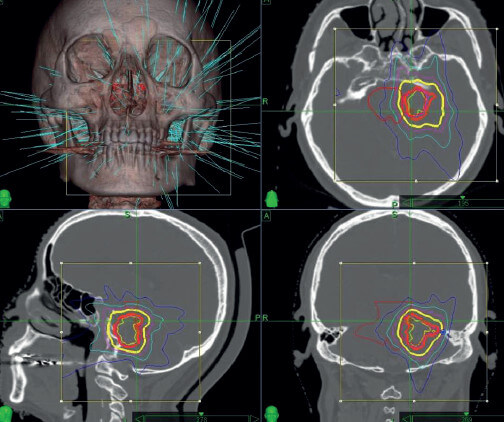

數碼導航刀放射治療

數碼導航刀放射手術適用於3厘米以下的腫瘤或手術後殘餘的腫瘤,老年、體質差的病人也適用。數碼導航刀放射治療相對風險比較小、康復快、治療時間短,一般3至7天便可。其治療效果與射線照射劑量有一定相關性,但腫瘤有囊性變化、腦幹受壓明顯者不建議此方法治療。其治療的原理是通過高能量射線照射殺死腫瘤細胞,或控制腫瘤細胞的生長。放射治療後短期內,腫瘤會有水腫、擴大的可能,因此術後短期內可能需要脫水降顱壓治療。醫學文獻分析結果顯示,數碼導航刀治療聽覺神經瘤的腫瘤控制率為85至100%,聽力保留率為60%,併發症發生率為5.6%。

伽瑪刀和數碼導航刀放射治療劑量的電腦規劃